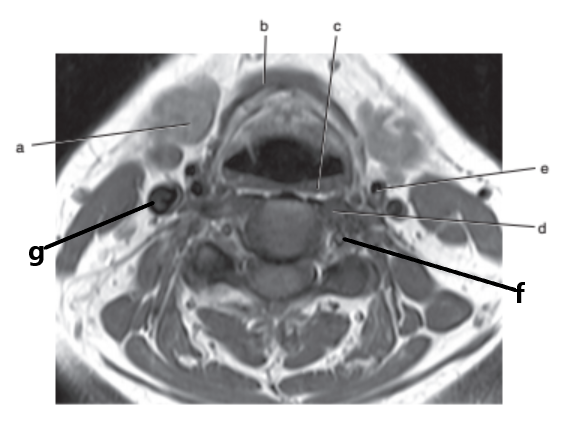

What anatomy is letter b ?

Epiglottis

What is letter a ?

Masseter muscle

Mandible

What is letter h ?

What is letter e ?